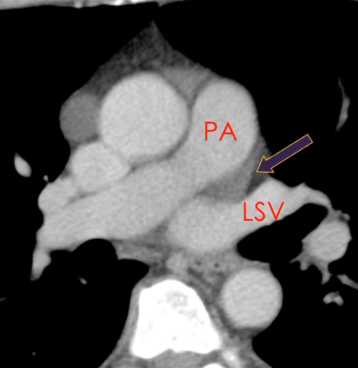

Récessus pulmonaire gauche

Sinus Oblique